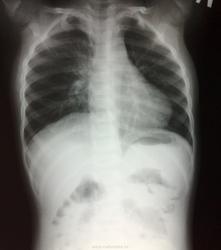

Ребенок 2-х лет откусил половину старинного градусника (который с ртутью).

Ребенок раскусил градусник.

Никогда не думал, что этот градусник уже "старинный". Куда себя заносить? Справа в брюшной полости есть округлый участок затемнения, возможно, это ртуть, но не уверен. Слушал лекцию одного московского токсиколога, там был случай суицида с введением ртути в вену. В результате она оказалась в артериях конечностей и на рентгенограммах выглядела как множественные круглые, продольно расположенные затемнения. Думаю, что и в данном случае ртуть распадется на множество мелких частей.

Вроде что-то похожее на ртуть маячит, если это не артефакты. Обычно ртуть выглядит так

А с легкими все нормально?Справа верхняя доля выглядит как-то подозрительно.

Много раз видел проглоченную детьми ртуть - она дает на снимках очень интенсивные тени, прямо свинцовой плотности, как и на картинках от Ola-la. У этого ребенка рентгеноконтрастных инородных тел не вижу - или уже ушли (когда кусал не указано), или не глотал. За аспирацию тоже данных не вижу. А относительно "старинности" термометра - другие пока не распространены в наших краях.

А почему такой корень справа? У детей так и должно быть?

Ртуть никогда не "мажет"...как здесь, форма должна быть правильной.

Согласился бы с обогащённым сосудистым рисунком. Но, похоже, снова банальный поворот или строго говоря, посредственная укладка вносят свой вклад в диагностику.(

обеднение легочного рисунка по периферии и изменения правого корня могут говорить о нарушении бронхопроходимости

у детей правый корень так обычно и выглядит